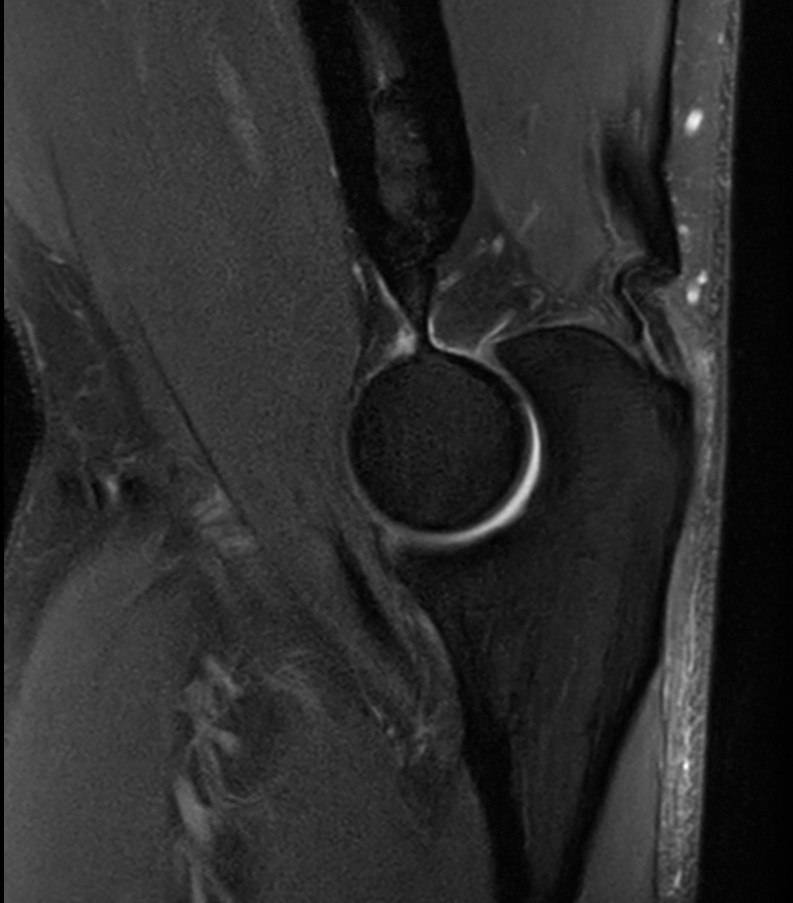

Sagittal PDw SPAIR